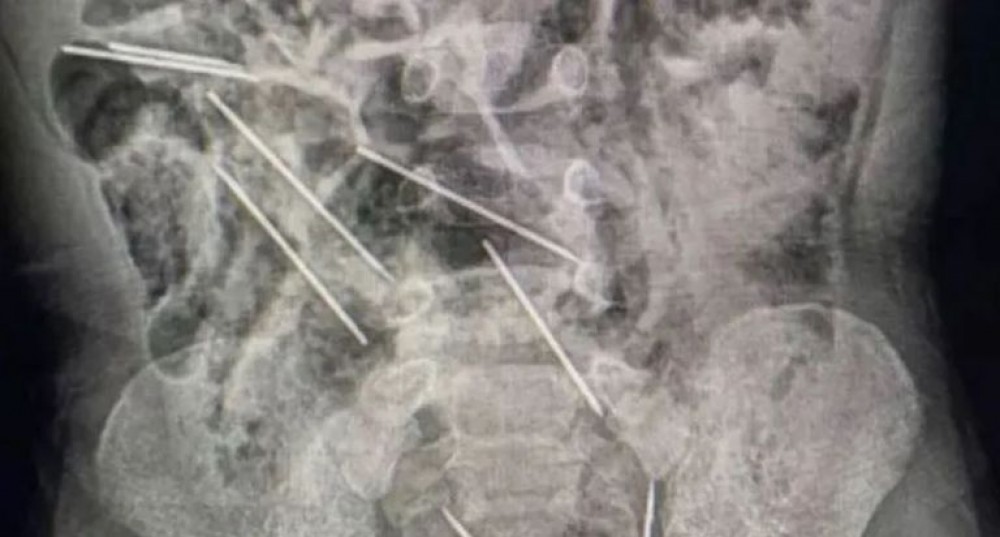

في شمال شرق بيرو، قام أطباء بإنقاذ حياة طفل يبلغ من العمر عامين بعدما ابتلع 8 إبر حقن أثناء لعبه.

أفاد الطبيب إفراين سالاسار بأنهم عندما قاموا بفتح بطن الطفل في غرفة العمليات، اكتشفوا وجود تلك القطع المعدنية وتبين أنها في الواقع إبر.